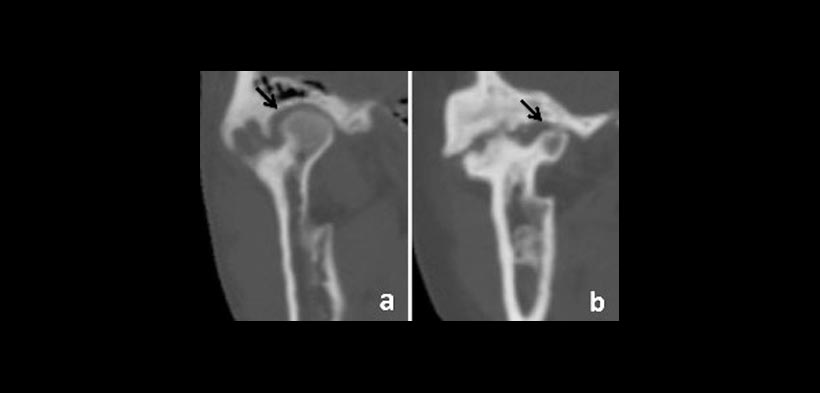

En el 2011, Yang et al, propusieron una clasificación más de anquilosis de la ATM en función del tamaño del cóndilo residual visto en tomografía computarizada (CT ). Así tenemos dos tipos de anquilosis de ATM con cóndilo residual:

-TIPO A2: Anquilosis con la fusión ósea en el lado lateral de la articulación, donde el fragmento condilar residual es más grande que la mitad de la cabeza del cóndilo en el lado medial (fig.1).

-TIPO A3: Es similar a A2 pero el fragmento condilar residual es menor que la mitad de la cabeza condilar (fig. 1).

Fig 1. Clasificación de la anquilosis traumática de ATM según Yang. a) Tipo A2, b) Tipo A3.